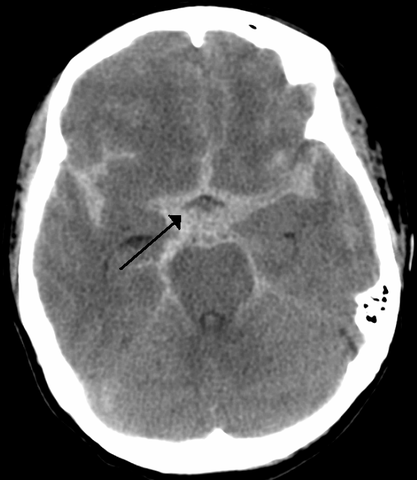

Headache is a common symptom encountered in the emergency department (ED), representing about 2% of all presenting complaints.(1) Subarachnoid hemorrhage (SAH) is a neurosurgical emergency and is diagnosed in about 1-3% of such ED patients. Guidelines for evaluation and diagnosis of subarachnoid hemorrhage published in 2009 emphasize the need to maintain a high level of suspicion for SAH in patients with an acute severe headache and recommend evaluation with head computed tomography (CT) scan followed by lumbar puncture (LP) if the CT scan is negative.(2)

Given the substantial morbidity and mortality associated with SAH, the timely application of diagnostic modalities with sensitivity approaching 100% is paramount. Traditionally, initial diagnostic evaluation for SAH begins with non-contrast head CT, followed by LP if the head CT yields negative results. However, there are many drawbacks associated with the LP, including patient pain, discomfort and anxiety, the potential for complications, as well as time constraints inherent to the ED. The following two studies evaluate the sensitivity of modern head CT in the evaluation of SAH and consider the possibility that an LP may not be necessary if a CT performed within a certain period of time from symptom onset can be shown to have adequate sensitivity for excluding SAH.

This prospective multicenter cohort study enrolled 3,132 alert, neurologically intact patients presenting with high risk headache. “Alert” was defined by a Glasgow coma score (GCS) of 15; “high risk” was defined as an atraumatic headache reaching maximal intensity within one hour or an atraumatic headache associated with syncope. The primary outcome was SAH, defined by the detection of subarachnoid blood on CT, xanthochromia identified in CSF, or any red blood cells detected in the final tube of CSF in conjunction with aneurysm identified on cerebral angiography.

Overall, of the 3,132 patient cohort, 240 (7.7%) were found to have SAH. A subset of 953 patients had head CT performed within six hours of headache onset; of these, 121 patients were diagnosed with SAH, and all cases were identified on head CT with 100% sensitivity (95% CI, 97-100%). At greater than six hours (n=2,179), the sensitivity was 85.7% (95% CI, 78.3-90.9%); the overall sensitivity of head CT among this cohort was 92.9% (95% CI, 89-95.5%). All studies were performed with third generation modern multi-slice scanners and interpreted by experienced local neuroradiologists or general radiologists who had access to pertinent clinical information but were blinded to patient participation in the study. Local laboratory technicians unaware of the study interpreted CSF for xanthochromia by visual inspection. Patients who did not have a definitive cause of their headache diagnosed in the ED were followed over six months; of the 1,931 patients in this category, 31 were lost to follow up, and none of the remaining patients were identified as having an SAH.

Overall, the study demonstrates that the modern generation of CT scanners are extremely sensitive (approaching 100%) for detection of SAH if obtained within six hours of headache onset and when interpreted by qualified radiologists. Further studies with similar results could help remove the requirement for LP in some patients with suspected SAH.